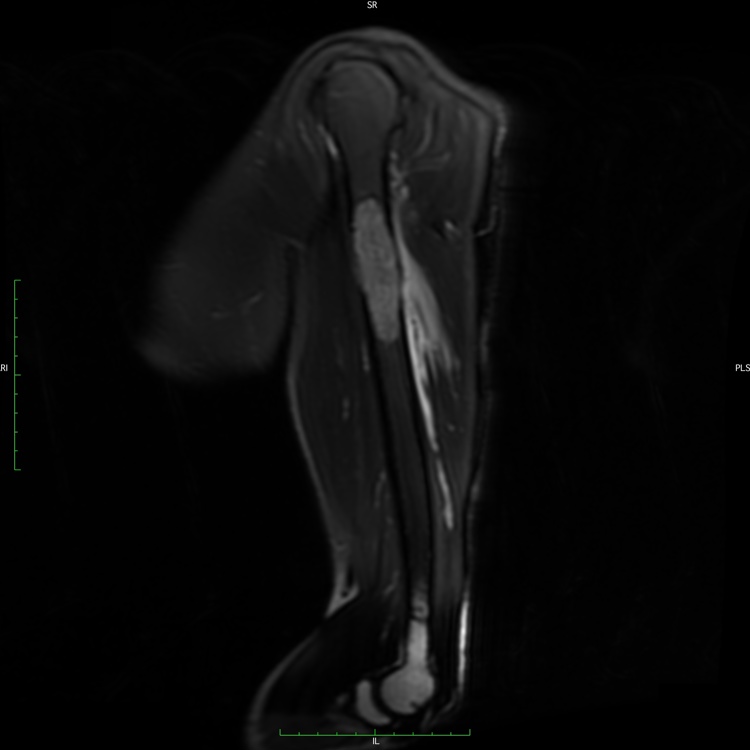

19D) Myeloma SAG T2 FATSAT

Radiographic imaging is used to help form a diagnosis of Myeloma. These include X-Ray, MRI, CT and Bone Scans